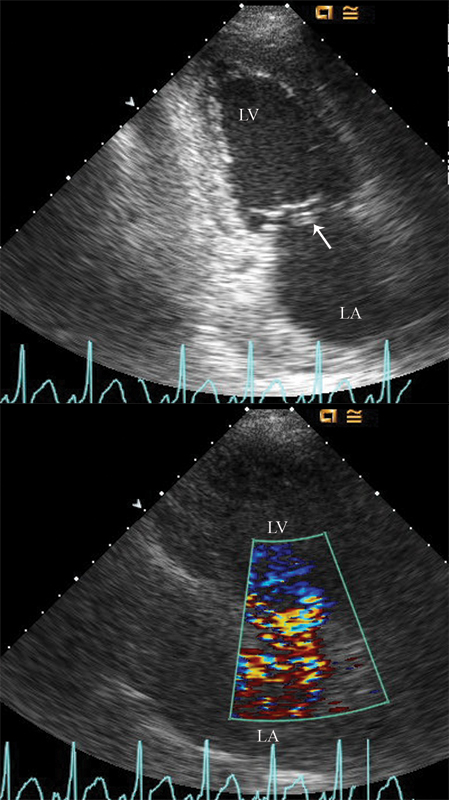

فحوصات تشخيصية لبعض امراض القلب والشرايين التاجية